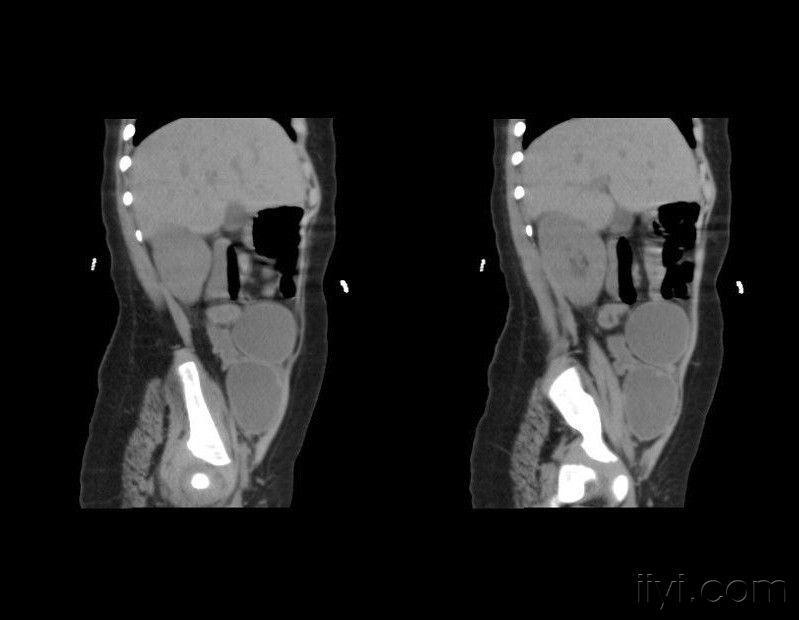

然后医生又看了看女子的腹部B超,显示子宫和卵巢存在着明显问题,看到这时,内分泌科专家心中基本已经有了答案,这是很典型的先天性肾上腺皮质增生症,但是眼前的证据暂时还不足以支撑诊断,于是专家又让她去做个肾上腺CT。结果出来后果然和专家预估的一模一样。

紧接着,专家又让女子去做一次染色体序列检测,果不其然染色体序列为“46XY”,这就意味着眼前的女生并不是一位女生,而是一位生理性的男生!当专家把这个消息告诉女子的时候,女子瞬间崩溃了,她怎么都不敢相信自己当了25年的女生,突然就变成了男生?